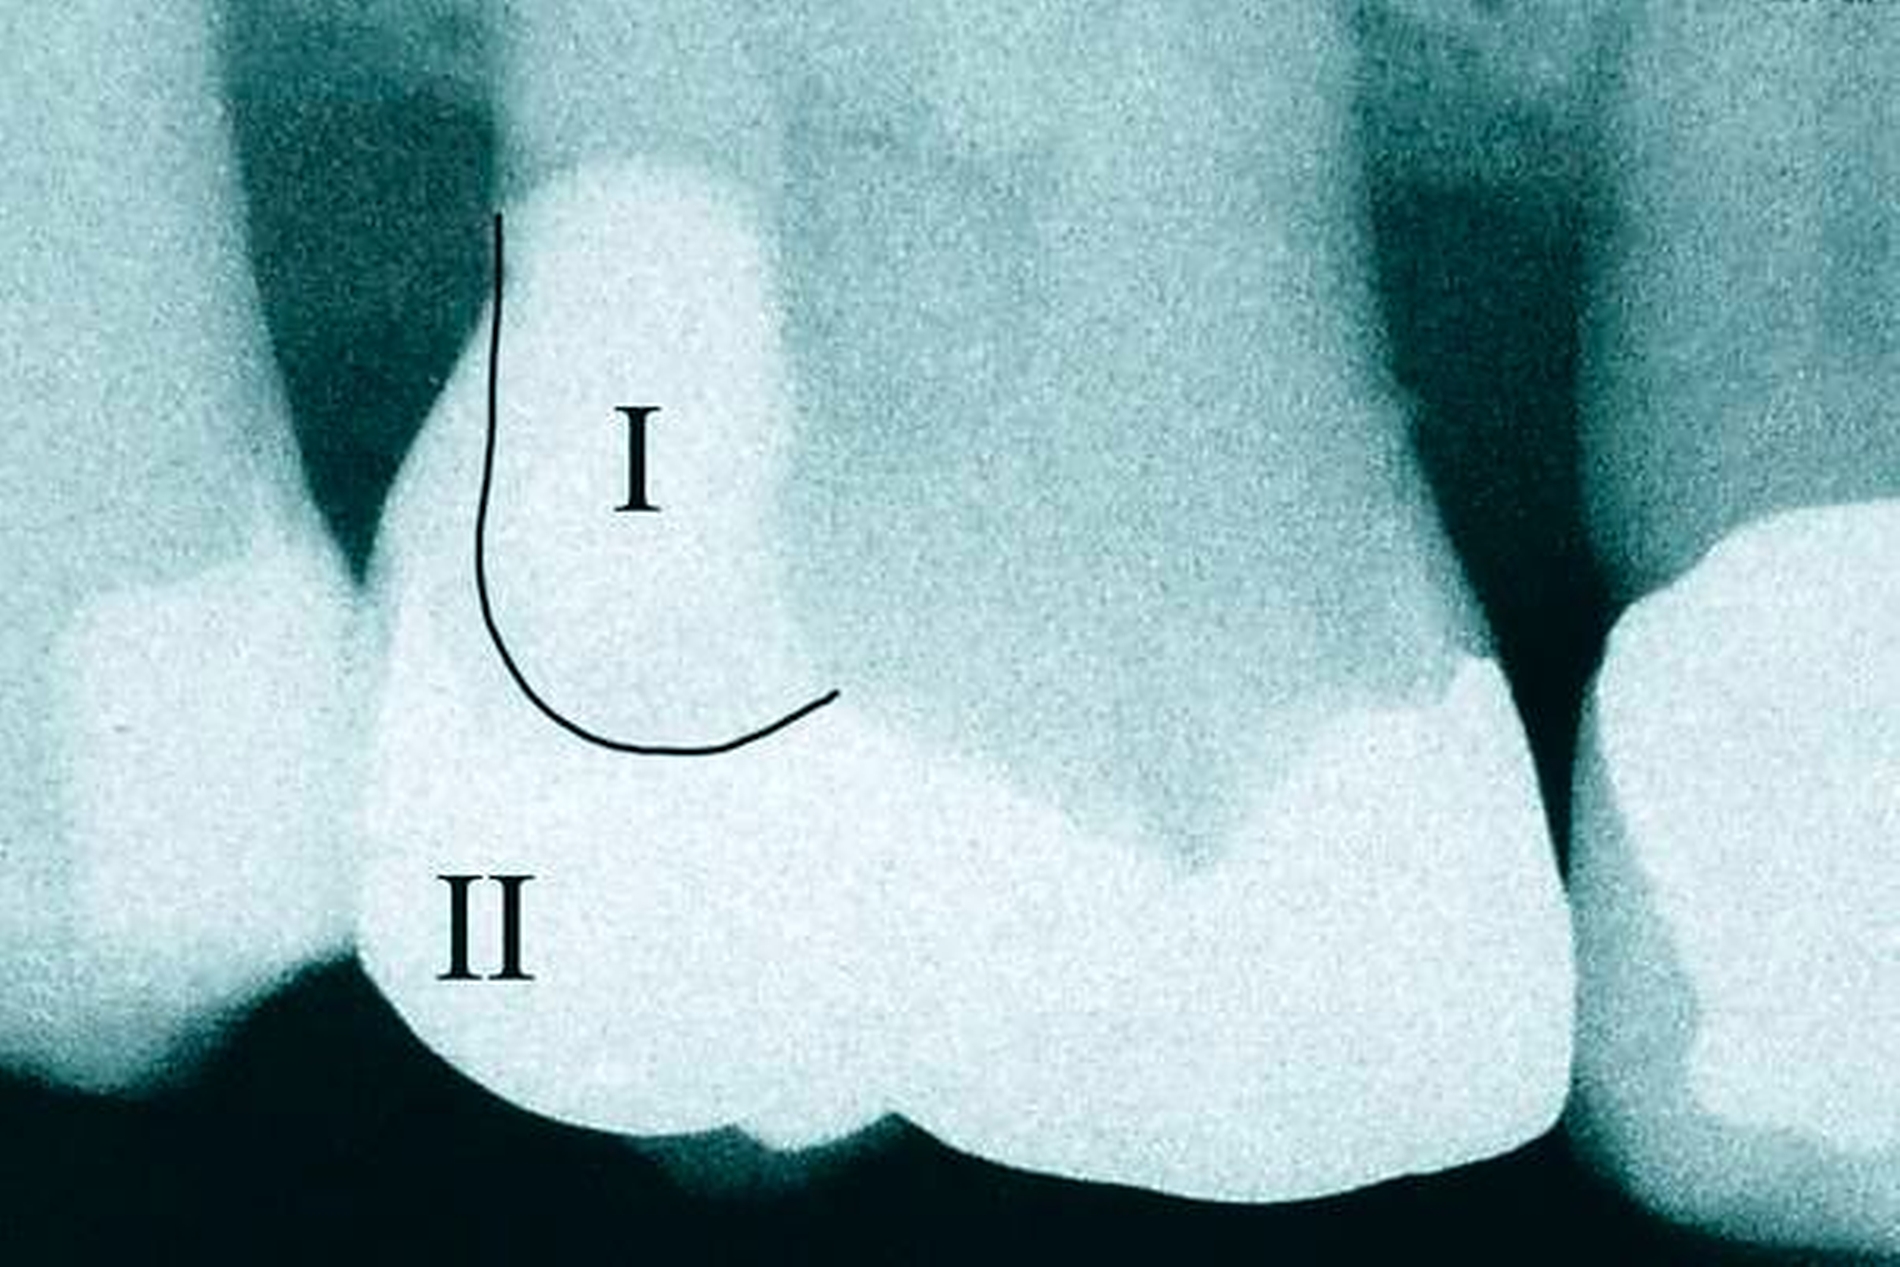

In den Abbildungen 1 bis 3 werden Optionen für frugale Interventionen auf restaurativem Sektor aufgeführt. Es handelt sich um direkte Vollüberkronungen im Frontzahnbereich (hier: hergestellt in R1-Technik / einphasig) (Abbildung 1), direkte Teilüberkronungen im Seitenzahnbereich (hier: hergestellt in R1-Technik / einphasig) (Abbildung 2), Reparatur-Restaurationen im Seitenzahnbereich (hier: hergestellt in R2-Technik / zweiphasig) (Abbildung 3). Technische Einzelheiten zur Vorgehensweise und den Ergebnissen sind an anderer Stelle beschrieben (Literatur siehe oben).

Am Beispiel von Abbildung 1 (stark zerstörte Zahnkrone eines Schneidezahns) kann das Prinzip der frugalen Intervention erläutert werden:

Früher wurde für die hier beschriebene Ausgangssituation folgendes Procedere gewählt:

Wurzelkanalbehandlung des vitalen Zahns als Voraussetzung für eine Stiftversorgung

Einsetzen eines Wurzelkanalstifts

Einsetzen einer indirekt gefertigten Stiftkrone

Durch die Erfolge der Adhäsiv- und Komposittechnik kann heute folgendermaßen vorgegangen werden:

Verzicht auf Wurzelkanalbehandlung / Erhaltung der Vitalität des Zahns

Verzicht auf Wurzelkanalstift

direkte minimalinvasive Kompositkrone (Verzicht auf indirekte Vorgehensweise)

Die potenziellen medizinischen und ökonomischen Vorteile dieser frugalen Intervention sind vielfältig:

Schonend: Die oralen Strukturen werden geschont und die Versorgung ist hinreichend stabil. Durch den Verzicht auf Wurzelkanalstifte wird das Wurzelfrakturrisiko reduziert. Zudem können Material-, Geräte- und Personalressourcen aus Praxis und Techniklabor, die beim klassischen Vorgehen anfielen, reduziert werden.

Bezahlbar: Hier ist anzumerken, dass die Kosten unter anderem von der zahnärztlichen Expertise abhängig sind: Zahnärzte, die mit direkten Restaurationen große Erfahrung haben, können zügiger und mit besserem Erfolg arbeiten als Kollegen mit geringerer Erfahrung auf diesem Gebiet; die Behandlung ist gleichwohl anspruchsvoll und deshalb nicht „billig“. Eine direkte Vorgehensweise kann, muss aber nicht automatisch zeit- und kostensparender sein als eine Versorgung mit indirekt hergestellten Werkstücken.

Gut genug: Ästhetische Feinheiten lassen sich bei direkten Restaurationen nicht immer in gleicher Perfektion einarbeiten wie bei indirekt gefertigten Kronen, auch die Stabilität des Hochglanzes lässt bei einigen Kompositpräparaten noch zu wünschen übrig. Andererseits erlauben die direkten Verfahren inzwischen mitunter sehr flexible Vorgehensweisen, die sich auch mit Farb- und Formkorrekturen von Zähnen kombinieren lassen. Die Erwartungen eines großen Teils der Patienten werden hinreichend erfüllt und die Nutzen-Risiko-Relationen wie auch die Aufwand-Kosten-Relationen erscheinen – wenn auch nicht durchgängig – so doch zumindest in vielen Fällen günstig.